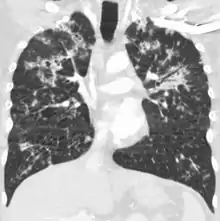

A case of miliary tuberculosis in an 82-year-old woman:

X-ray, 13 days after onset, showing bilateral interstitial infiltrates